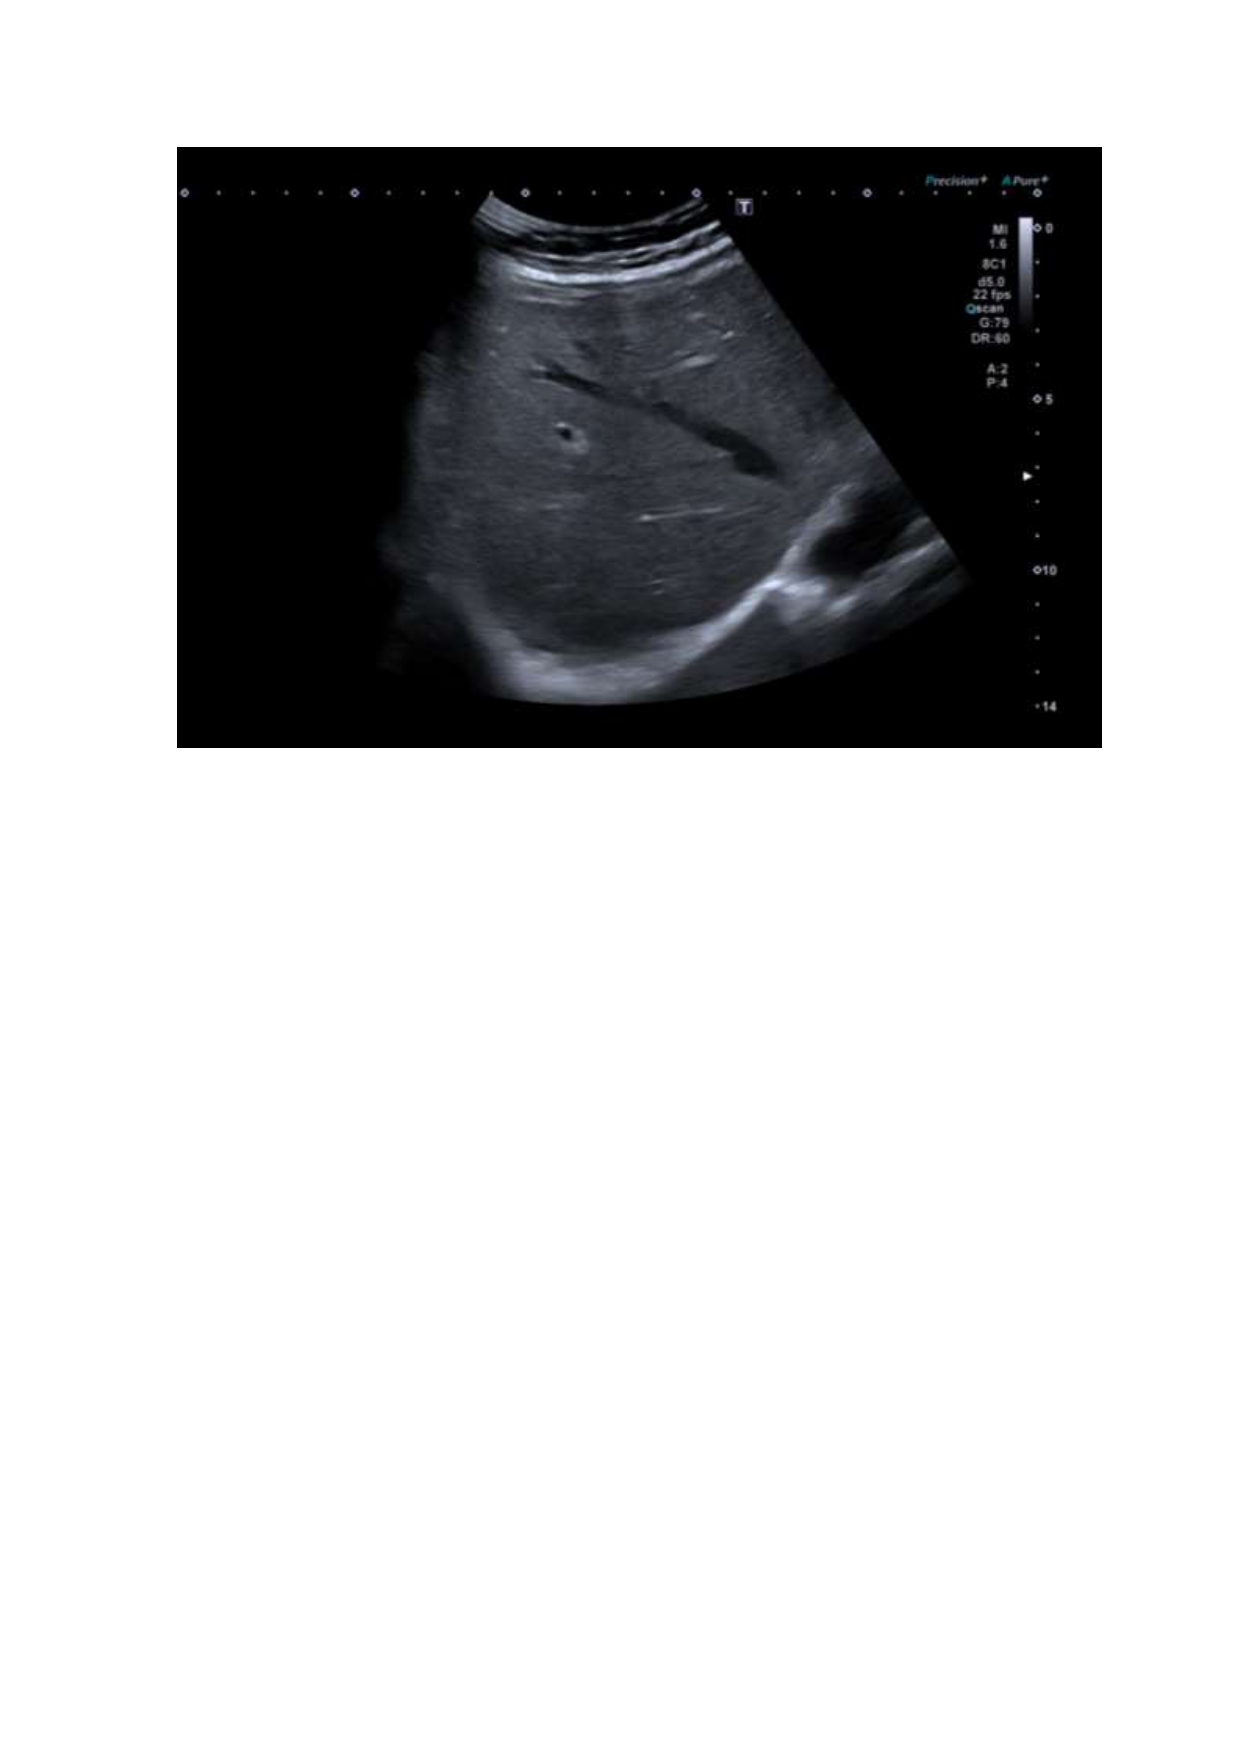

Se realizó ecografía a pie de cama que objetivó: Hígado de tamaño, contornos y ecogenicidad conservados, sin delimitar lesiones focales Sin líquido libre intraperitoneal.